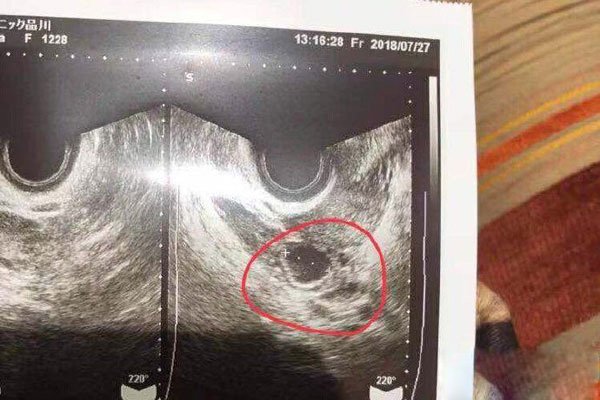

蒋劲夫的家暴已经是变得人尽可知,尽管很多明星朋友是表示支持蒋劲夫,也是认为他肯定是可以得到自己公平,但是很多事情不是我们看到那么简单,女方中浦悠花使用怀孕这样一个手段进行骗婚,还进行了敲诈,更加意外的情景还出轨,已经是到了这样一个地步,女方步步急逼应该是认为蒋劲夫会维护自己名誉,没有想到自己会被家暴吧!